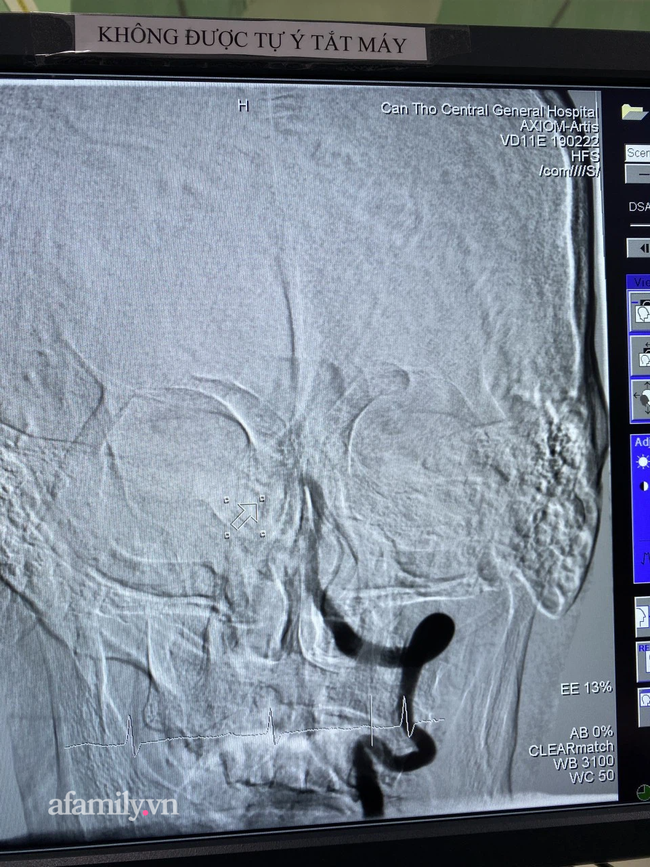

Ngày 1/3, bác sĩ Phạm Thanh Phong, Phó Giám đốc Bệnh viện Đa khoa Trung ương Cần Thơ (BVĐKTWCT) cho biết, các bác sĩ BV vừa can thiệp thành công cứu một bệnh nhân đột quỵ nặng với thời gian tái thông hoàn toàn động mạch bị tắc trong 10 phút.

Kết quả chụp CT-scan não phát hiện bệnh nhân bị tắc động mạch thân nền từ vị trí hợp lưu đến đỉnh thân nền, nguy cơ tử vong rất cao nếu không can thiệp tái thông mạch máu. Đồng thời nếu can thiệp muộn thì di chứng rất nặng nề, bệnh có thể sống đời sống thực vật hoặc liệt tứ chi.

Ekip can thiệp nội mạch do TS.BS Hà Tấn Đức, Trưởng khoa đột quỵ và BS Trần Công Khánh, Phó khoa Chẩn đoán hình ảnh thực hiện can thiệp. Trong 10 phút, ekip đã tái thông hoàn toàn động mạch bị tắc, hút ra được rất nhiều huyết khối.